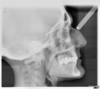

Les radios avant le traitement